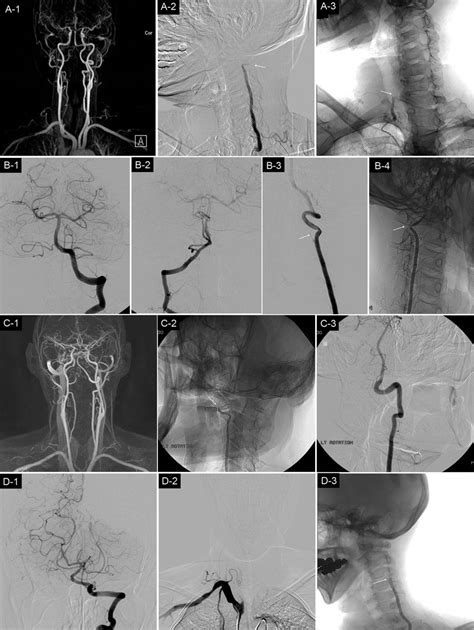

• Digital Subtraction Angiography (DSA): Considered the "gold standard," this invasive procedure involves injecting contrast dye to map the arteries with high resolution.

3. Endovascular Stenting: A minimally invasive procedure where a small mesh tube is placed inside the artery to hold it open and restore blood flow.